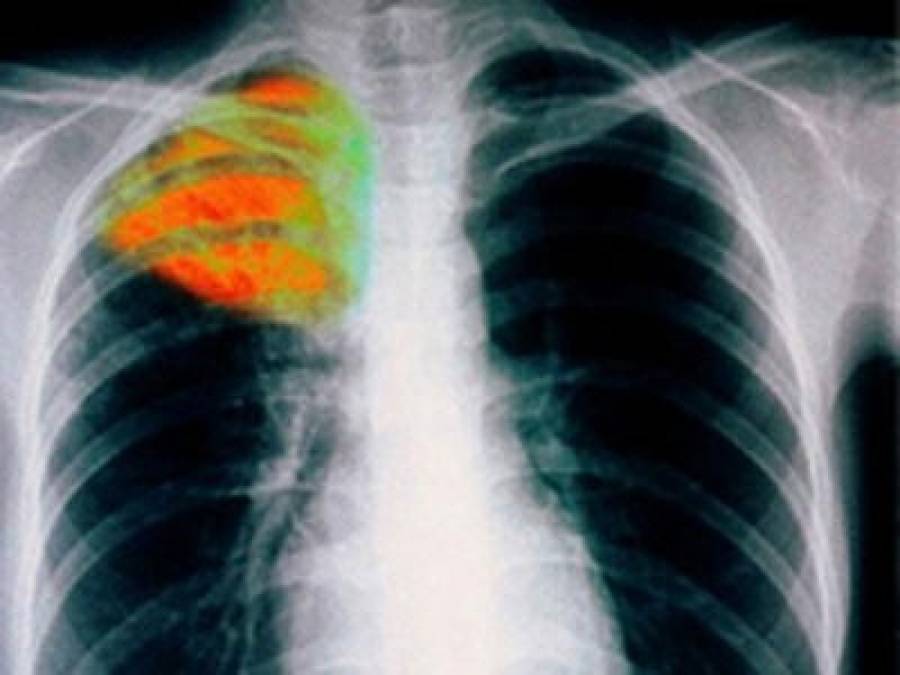

Παιδιά μικρής ηλικίας (<4 ετών), τα οποία έχουν στενή επαφή με πάσχοντα από μεταδοτική φυματίωση, πρέπει να εξετάζονται και να λαμβάνεται λεπτομερές ιστορικό για την ύπαρξη συμπτωμάτων. Πρέπει επίσης να υποβάλονται σε ακτινογραφία θώρακος και δερμοαντίδραση Mantoux. Εάν όλα είναι αρνητικά, χορηγείται χημειοπροφύλαξη με ισονιαζίδη για χρονικό διάστημα 3 μηνών από την τελευταία επαφή με τον πάσχοντα, οπότε επανεξετάζονται με δερμοαντίδραση Mantoux. Κατά το χρόνο αυτό, εάν η Mantoux παραμένει αρνητική σημαίνει ότι το εξεταζόμενο παιδί δεν έχει μολυνθεί και η χημειοπροφύλαξη με ισονιαζίδη διακόπτεται. Σε αντίθετη περίπτωση συνεχίζει για 6-9 μήνες.